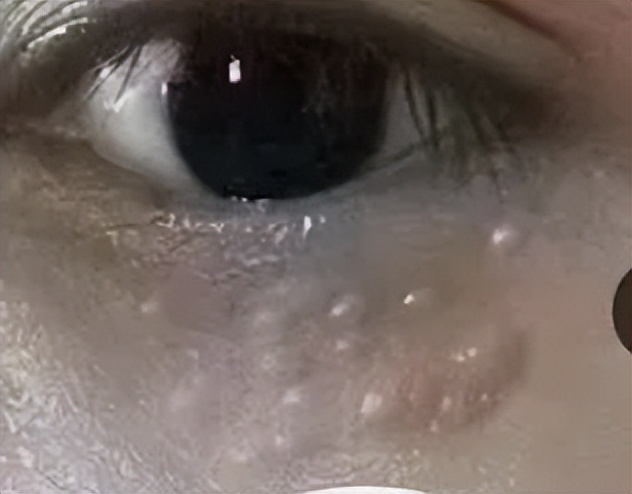

这些小疙瘩,医生把它叫做栗丘疹,是一种良性囊肿,可发于任何年龄,大多会出现在女性的群体之中。

具体表现,就是白色或淡黄色圆形小疙瘩,直径1-2mm,类似一颗小米粒埋入皮内,如果用针挑破,会挤出少量白色角质物。